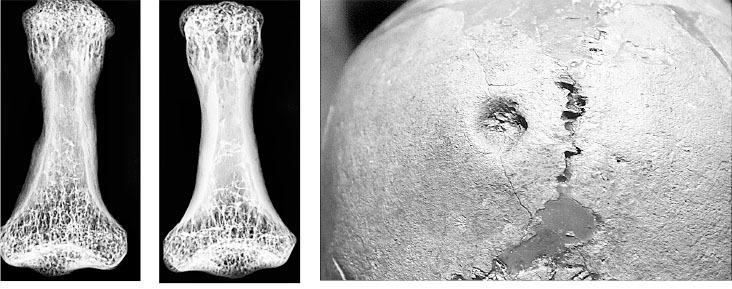

Давным-давно, в 2004 году я опубликовала книжку под названием «Трепанации в древнем мире и культ головы». Я благодарна издательству «АСТ» за предложение переиздать ее спустя столько лет. Но, когда дело дошло до работы с текстом, стало ясно, какое мощное развитие получило это научное направление за минувшие годы. Возникли новые отрасли знания, такие как палеогеномика, изучающая древнюю ДНК. Это позволяет наиболее объективно оценить вопросы происхождения разных групп людей и их связи между собой. Благодаря разработке методов датирования археологических объектов уточнились и изменились наши знания о хронологии ушедших культур. Новые раскопки позволили выявить большое число случаев хирургического вмешательства в прошлом, в том числе, на территории России. В арсенал палеопатологов, изучающих трепанации и болезни древнего населения, прочно вошли современные методы радиологии. Например, компьютерная томография и микрофокусная рентгенография стали рутинными процедурами, и они позволяют судить о причинах трепанирования и о течении послеоперационного процесса.

С этим связаны определенные трудности в работе экспертов. Не имея в руках истории болезни, не так просто отличить прижизненные операции, вскоре после которых пациент скончался, от посмертных вскрытий (Рис. 11). Разработана подробная дифференциальная диагностика, предусматривающая, что «дополнительные» отверстия в голове человека могут появиться под воздействием травм, болезней или даже иметься от рождения.